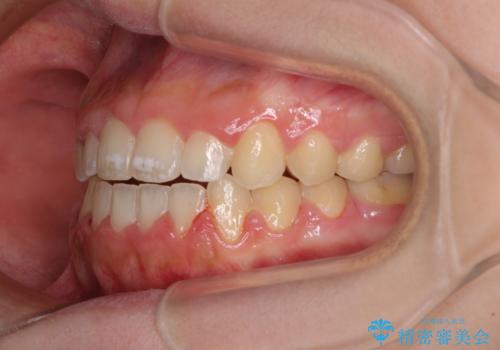

上顎骨を拡大したことで、下顎の歯列を上顎が受け入れられるようになりましたが、インビザラインでは咬み合わせを改善させることができなかったため、ワイヤー矯正にて仕上げることとしました。

ワイヤーを使用したものの、上下前歯のオープンバイトがなかなか改善されませんでしたが、患者希望により治療終了となりました。